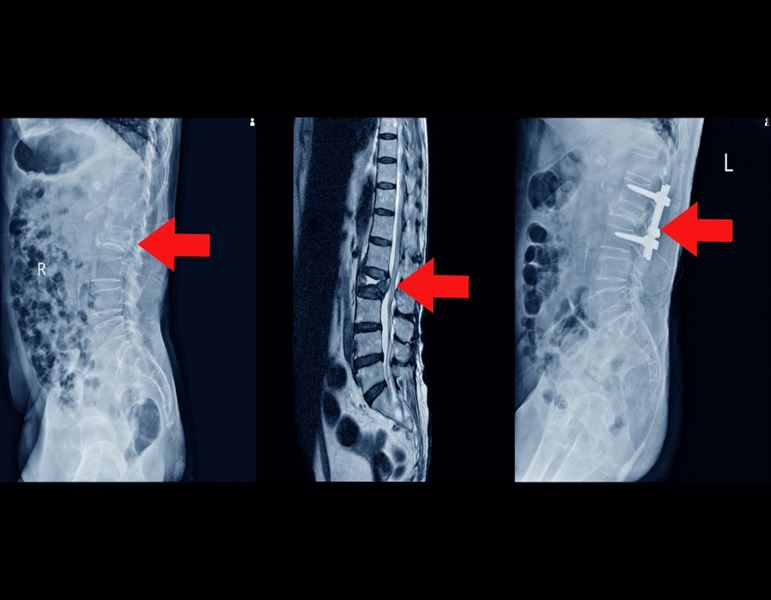

למידע נוסף על טיפול אלקטרומגנטי לבלט דיסק לחצו !

למידע נוסף על טיפול אלקטרומגנטי לפריצת דיסק לחצו !